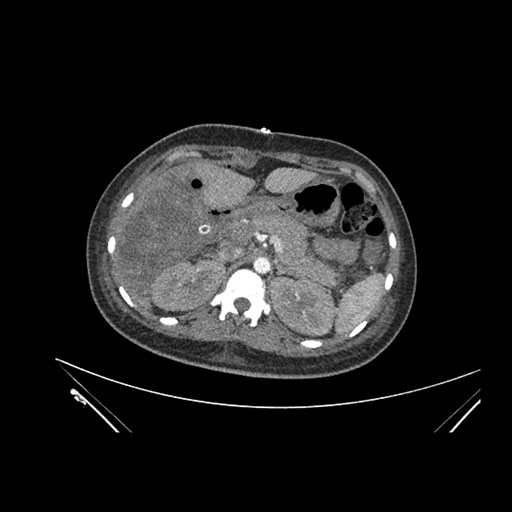

Axial Arterial

Imaging analysis

Based on initial findings, which issue(s) would you be most concerned about?